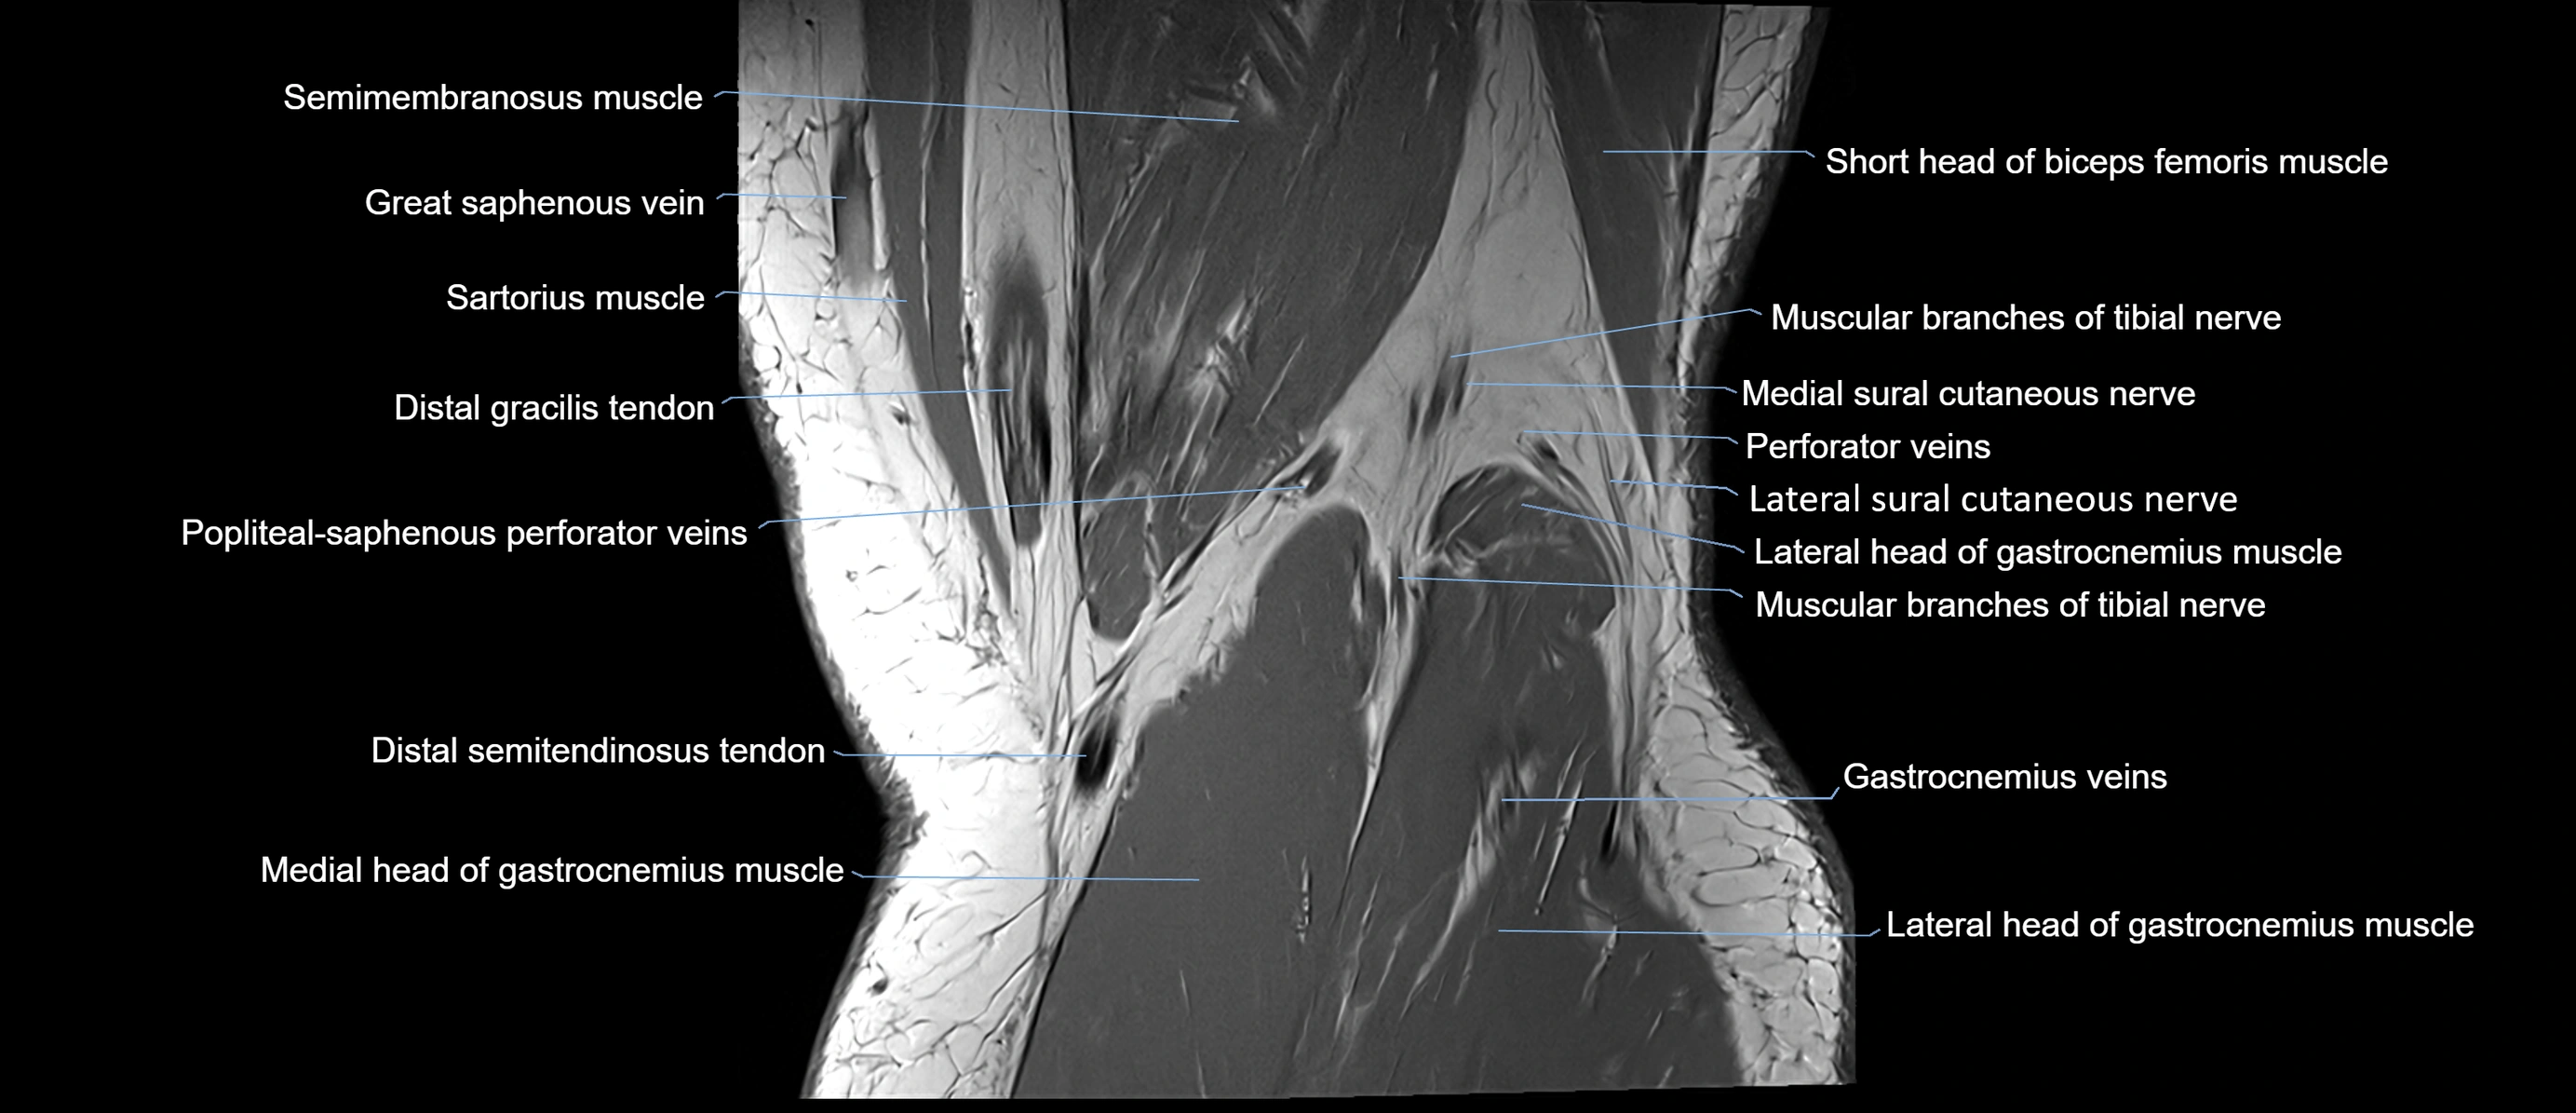

- Gracilis tendon (Distal)

- Lateral head of gastrocnemius muscle

- Lateral sural cutaneous nerve

- Medial head of gastrocnemius muscle

- Medial sural cutaneous nerve

- Muscular branches of tibial nerve

- Popliteal–Saphenous perforating veins

- Sartorius muscle

- Semimembranosus muscle

- Soleus muscle

- great saphenous vein